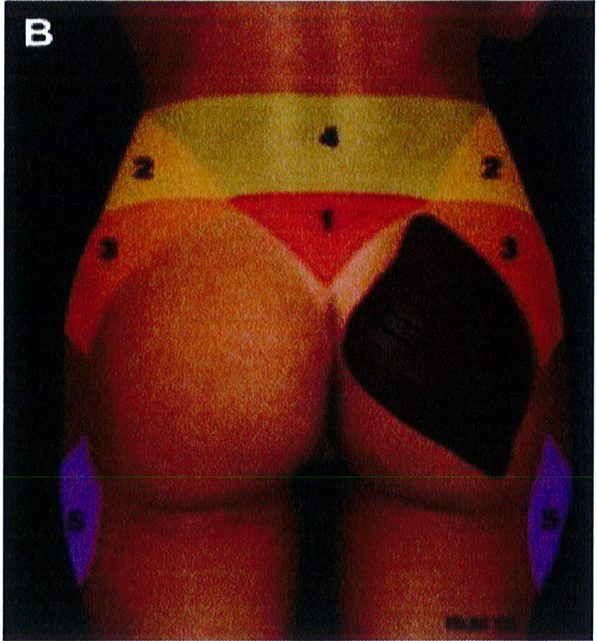

Hình. 2. (A) 10 đơn vị thẩm mỹ vùng sau được mô tả. (B,C) Sau khu vực quan trọng xác định hình dạng khung; bao gồm vùng 1 – 5 và vùng 8. (C) Vùng 8 có thế yêu cầu ghép mô mỡ để tạo đường bờ đẹp (Từ bài báo của Mendieta CG. Gluteal reshaping. Aesthet Surg J 2007;27(6):641-55)

Aesthetic Unit/Zones:Đơn vị thẩm mỹ vùng mông.

1.Sacrum V-zone: Vùng cũng chữ V. 2.Flank: Hông.

7.Diamond zone:inner gluteal/leg injection: Vùng hình thoi: Vùng đùi trong/vùng hút mỡ. 8.Mid-lateral buttock point:Điểm C. 9.Inferior gluteal /posterior leg junc- tion: Mặt sau đùi/mặt dưới mông. 10.Upper back: Lưng.

Aesthetic Unit/Zones:Đơn vị thẩm mỹ vùng mông. 1.Sacrum V-zone: Vùng cũng chữ V. 2.Flank: Hông. 3. Upper buttock : Mông trên, 4. Lower back: Thắt lưng. 5.Outer leg : Bờ ngoài đùi. 6. Gluteus: Mông.

8.Mid-lateral buttock point:Điểm C. 9.Inferior gluteal /posterior leg junc- tion: Mặt sau đùi/mặt dưới mông. 10. Upper back: Lưng.

3.Upper buttock : Mông trên, 4. Lower back: Thắt lưng. 5.Outer leg : Bờ ngoài đùi. 6. Gluteus: Mông.